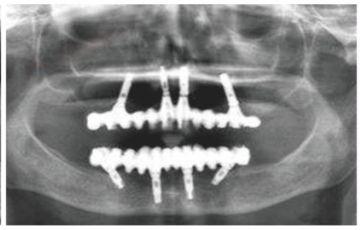

種牙后X光片,未戴冠。

種牙后X光片,戴冠。

通過(guò)X光片可以看到,醫(yī)生雖然盡量設(shè)計(jì)連冠種植,但還是用了十七個(gè)植體,盡管已經(jīng)是多次調(diào)整后的精簡(jiǎn)方案,但手術(shù)時(shí)長(zhǎng)依然長(zhǎng)達(dá)一天。位老先生之前在另一家醫(yī)院咨詢時(shí),醫(yī)生給的方案是種二十二個(gè)植體,光是種植費(fèi)用就令人大呼“害怕”了。